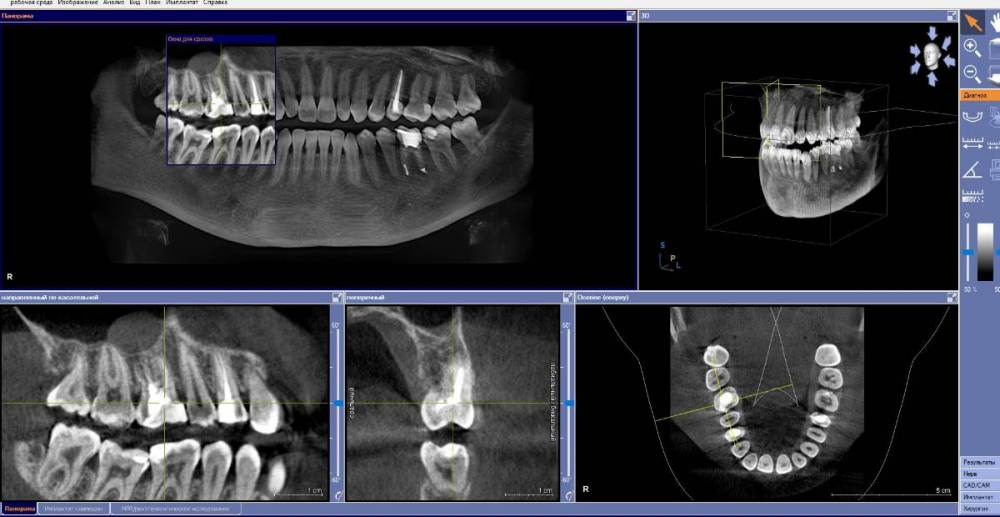

anishuma Опубликовано 1 сентября, 2021 Поделиться Опубликовано 1 сентября, 2021 (изменено) Здравствуйте, прошу помочь разобраться с моими КТ и направить для дальнейших действий. История такая: в 2018 году шестой зуб сверху справа был депульпирован. Долго сохранялись боли при нажатии, при жевании, зуб реагировал на холодной и горячее. Врач, который лечил, заверила что это постпломбировочные боли и скоро пройдет. Коронку побоялась ставить из-за этих болей. Затем примерно через год отлетел кусочек пломбы. Зуб восстановили для дальнейшей установки коронки. На данный момент есть ощутимая реакция на давление, при жевании, при чистки зубной щеткой. Зуб реагирует на холодное-горячее. Один врач сказал, что не видит показаний для перелечивания каналов. Другой врач настаивает на удалении зуба. Подскажите, пожалуйста, где истина, и возможно ли сохранить зуб. Изменено 1 сентября, 2021 пользователем anishuma Ссылка на комментарий

Bier Опубликовано 2 сентября, 2021 Поделиться Опубликовано 2 сентября, 2021 похоже что есть гранулема на корне 2 Ссылка на комментарий

St. Опубликовано 3 сентября, 2021 Поделиться Опубликовано 3 сентября, 2021 +1 к гранулеме. Я бы перелечивала каналы. Но нужно в процессе будет смотреть нет ли трещин в корне. Ссылка на комментарий